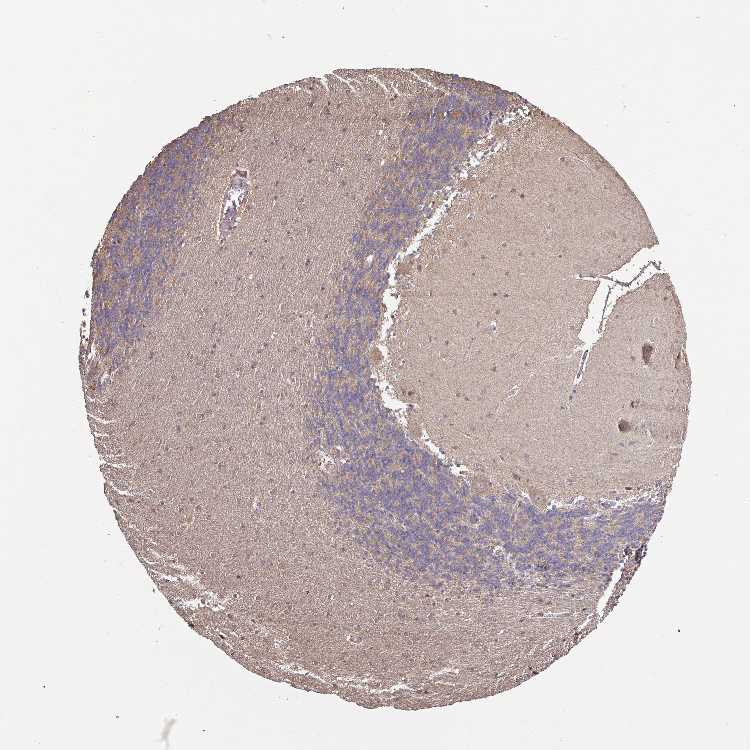

BRAIN CEREBELLUM Show tissue menu

CEREBELLUM - Expression summary

CEREBELLUM - Antibody stainingi

Antibody staining in the annotated cell types in the current human tissue is reported as not detected, low, medium, or high, based on conventional immunohistochemistry profiling in selected tissues. This score is based on the combination of the staining intensity and fraction of stained cells.

Each image is clickable and will lead to virtual microscopy that enables deeper exploration of all samples and also displays staining intensity scores, fraction scores and subcellular localization as well as patient and tissue information for each sample.

Antibody HPA053295Antibody HPA060535

Purkinje cells MediumLow

Cells in granular layer Not detectedNot detected

Cells in molecular layer LowLow